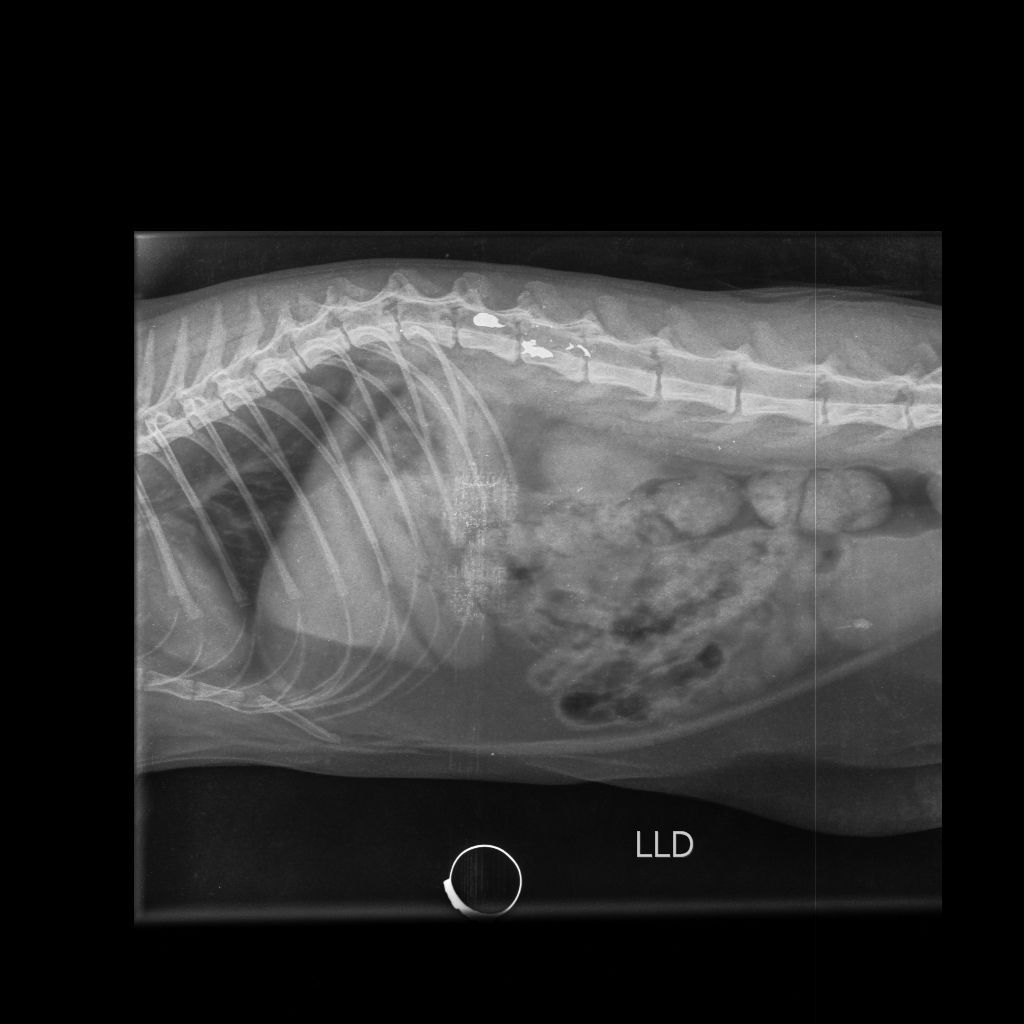

Após ser ferida, Morgana foi socorrida e encaminhada para atendimento veterinário na clínica Vida Pets, onde passou por exames e recebeu os cuidados necessários. Apesar dos esforços da equipe médica e do acompanhamento especializado, o animal não resistiu às consequências do ferimento.